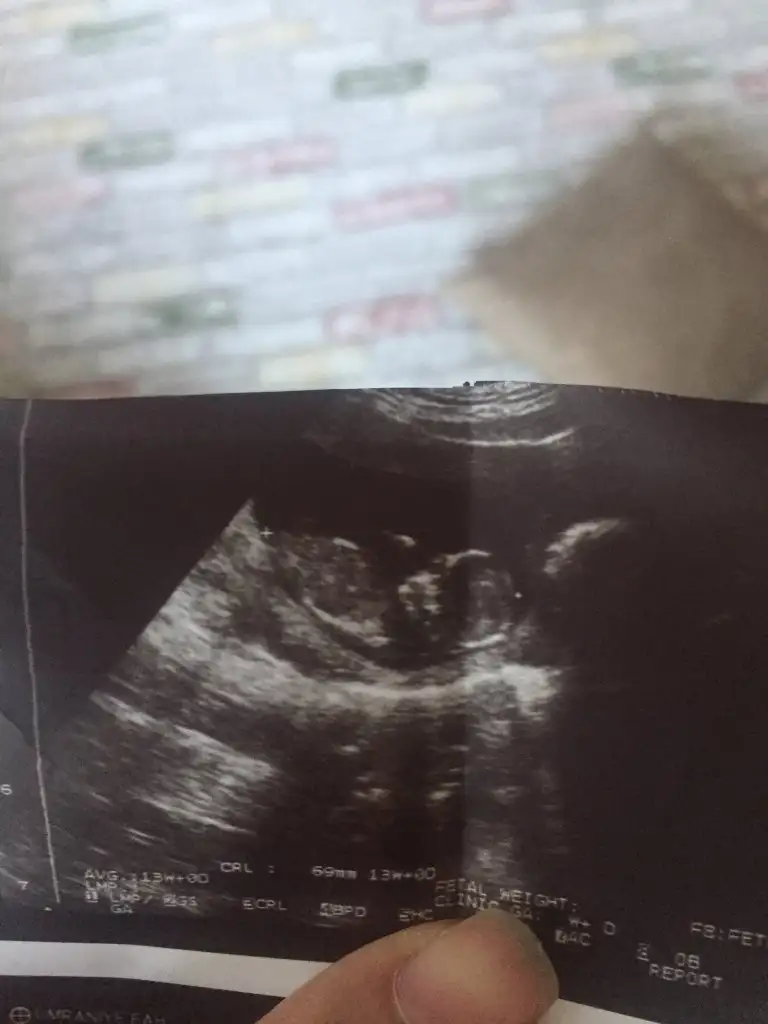

Sevgili @ıkrameyra cinsiyet tahmini alabilir miyim 🌹💕

BDA5C7BD-3496-4BB1-A970-938708FDFC4E.jpeg

Eklentiler

• 61A9F4EF-9683-43B4-B5BD-00CCB355CF56.webp

61A9F4EF-9683-43B4-B5BD-00CCB355CF56.webp

28,5 KB · Görüntüleme: 40

• C8D7EF01-26BB-4FC3-99CF-7FA7C7BDCC8C.webp

C8D7EF01-26BB-4FC3-99CF-7FA7C7BDCC8C.webp

37,8 KB · Görüntüleme: 49